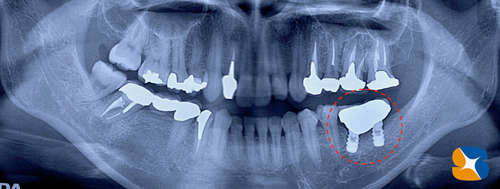

レントゲンで確認すると、かなり奥に傾いてインプラントが移植させていることが確認できます。

精密なレントゲン撮影を行うと、やはりインプラントを支える周囲の骨が、溶けて無くなっていました。